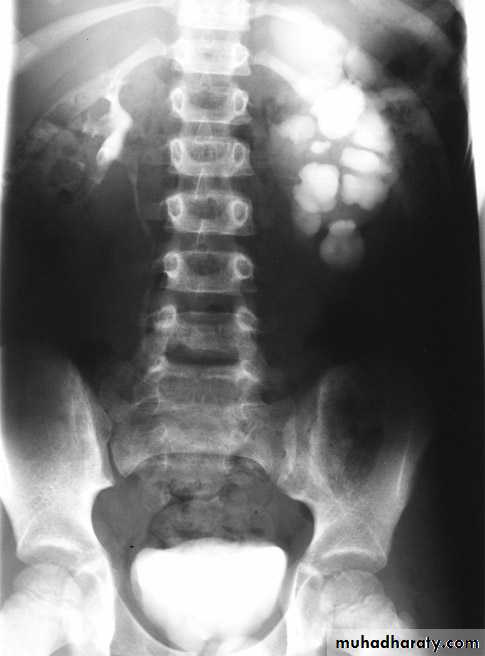

Horse shoe kidney -Kidneys may fail to separate.

-Almost invariably the lower poles remain fused.

-The kidneys axes are more parallel to the spine and malrotated.

-Diagnosis can be made by plain x-ray in some cases.

-US, CT scan and MRI can better demonstrate the anatomy and morphology hence the diagnosis.

-May be an incidental finding.

-PUJ obstruction and calculi formation are common .

IVU shows

1. The kidneys at low position .

2.Close to the spine with long axis parallel to the spine .

3. Malrotation manifested by medially directed calyces.

4- The renal pelvis and ureters are anterior and lateral in position .